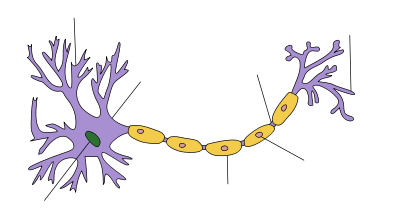

Myelin is a fatty white substance that surrounds the axon of some nerve cells, forming an electrically insulating layer. It is essential for the proper functioning of the nervous system. It is an outgrowth of a type of glial cell.

Schwann cells supply the myelin for the peripheral nervous system, whereas oligodendrocytes, specifically of the interfascicular type, myelinate the axons of the central nervous system. Myelin is considered a defining characteristic of the (gnathostome) vertebrates, but myelin-like sheaths have also been seen in some invertebrates, although they are quite different from vertebrate myelin at the molecular level. Myelin was discovered in 1854 by Rudolf Virchow.[2]

Myelin is made by different cell types, and varies in chemical composition and configuration, but performs the same insulating function. Myelinated axons are white in appearance, hence the "white matter" of the brain. Myelin helps to insulate the axons from electrically charged atoms and molecules. These charged particles (ions) are found in the fluid surrounding the entire nervous system. Under a microscope, myelin looks like strings of sausages.

1. Axon

2. Nucleus of Schwann Cell

3. Schwann Cell

4. Myelin Sheath

5. Neurilemma

The main purpose of a myelin layer (or sheath) is to increase the speed at which impulses propagate along the myelinated fiber. Along unmyelinated fibers, impulses move continuously as waves, but, in myelinated fibers, they "hop" or propagate by saltatory conduction. Myelin decreases capacitance and increases electrical resistance across the cell membrane (the axolemma). Thus, myelination helps prevent the electric current from leaving the axon. It has been suggested that myelin permits larger body size by maintaining agile communication between distant body parts.[6]

Myelinated fibers lack voltage-gated ion channels (approximately 25 μm−2) along the myelinated internodes, exposing them only at the nodes of Ranvier. Here, they are found far more abundantly (between 2,000 and 12,000 μm−2).[7] Myelinated fibers succeed in reducing sodium leakage into the extracellular fluid (ECF), maintaining a strong separation of charge between the intracellular fluid (ICF) and the ECF. This increases sodium’s ability to travel along the axon more freely. However, the sodium diffuses along the axolemma rapidly, but is decremental by nature. The sodium cannot trigger the opening of the voltage-gated sodium channels as it becomes weaker. The nodes of Ranvier, being exposed to the ECF every 1 mm or so, contain large amounts of voltage-gated sodium channels, and allow enough sodium into the axon to regenerate the action potential.[8] Each time the action potential reaches a node of Ranvier, it is restored to its original action potential (+35 mV).[7]